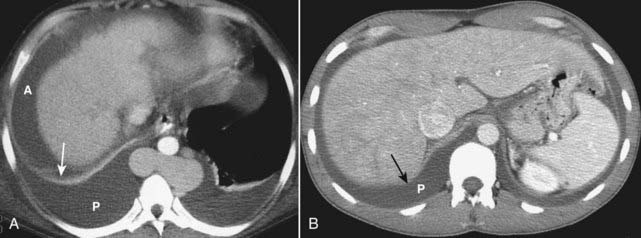

image

Figure 18-29 Cirrhosis with portal hypertension, CT.

Portal hypertension can lead to dilated vessels around the stomach, splenic hilum (solid white arrows), and esophagus representing varices. Splenomegaly may develop (S). There is characteristic enlargement of the caudate lobe (C) relative to the right lobe of the liver (solid black arrow), especially in alcoholic cirrhosis.

imageRecognizing cirrhosis of the liver on CT:

image Early in the disease, the liver may demonstrate diffuse fatty infiltration. As the disease progresses, the liver contour becomes lobulated. The liver shrinks in volume with the right lobe characteristically becoming smaller while the caudate lobe and left lobe become disproportionately larger, especially in alcoholic cirrhosis (Fig. 18-29).

image There is a mottled, inhomogeneous appearance to the liver parenchyma following intravenous contrast enhancement due to a mixture of regenerating nodules, focal fatty infiltration, and fibrosis.

image Portal hypertension may develop which can lead to dilated vessels around the stomach, splenic hilum, and esophagus representing varices.

image Splenomegaly may develop.